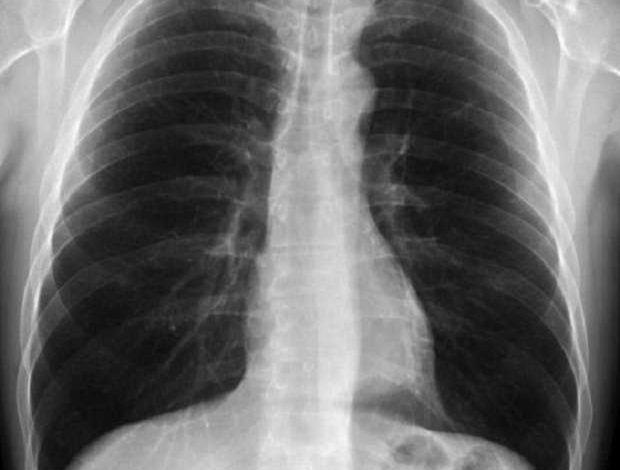

أصيبت امرأة يابانية بأضرار كبيرة في رئتيها بعد أن تسلل فيرس كورونا إلى جسدها، ولإصلاح الوضع، قام الأطباء بما قالوا إنها أول عملية زراعة رئة في العالم لمصاب بفيروس كورونا عن طريق الأنسجة.

وبات معروفا أن مرض “كوفيد-19” يسبب تلفا حادا في الرئة لبعض المصابين به، ولعلاجهم تمت عمليات زراعة رئات لهم لمساعدتهم على التعافي.

وتسببت مرض “كوفيد-19” في أضرار كبيرة لرئتين، وتطلبت عملية زرع رئة حتى تتمكن من العودة إلى الحياة الطبيعية.